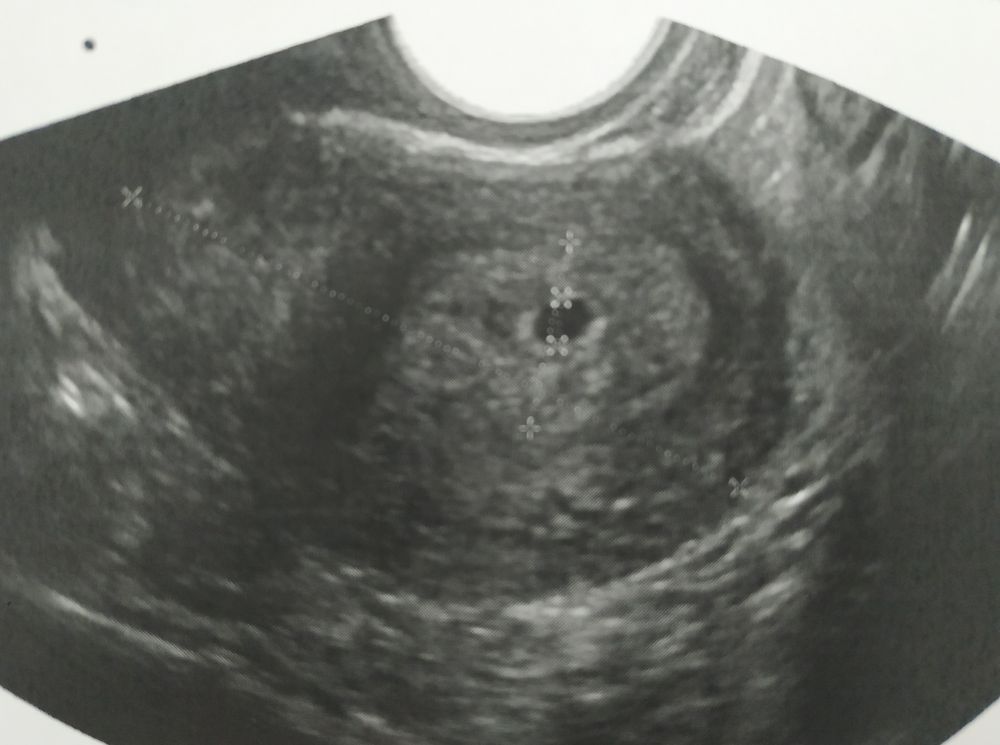

УЗИ. Беременность или нет?

Была сегодня на УЗИ. Срок 6 акушерских недель. Беременность не подтвердили. В матке образование 4 мм. Плодное яйцо под вопросом. Врач сказала, что пока не понятно, может через неделю это превратится в беременность.

Ну это ПЯ 100% даже что-то внутри есть. Только да, для этого сроко слишком маленькое.

Ну видимо беременность, раз у вас результат в кружочке))